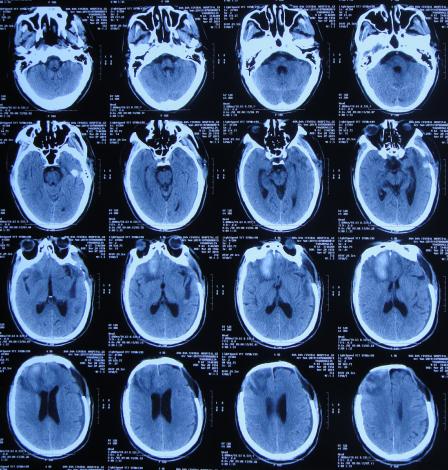

2020年3月18日(颅脑外伤开颅术后149天即颅骨修补术后95天即第2次脑室腹腔分流术后62天,先后经4家医院治疗后仍意识模糊,大小便*禁失**,脑积水,间断发热近2月)转住入李小勇脑脊液科。入院时:意识模糊,大小便*禁失**,体重较前明显减轻,体温高38度左右;头部可见引流管走向;右侧肢体活动差些;鼻饲流食( 图-30 );入院时头颅CT示颅骨修补术后、脑室引流术后仍脑积水,有水肿( 图-31 )。

图-30: 2020年3月18日入院时

图-31: 2020年3月18日头颅CT

入院次日拔除了原脑室腹腔分流管+脑室外引流术( 图-32 )。

图-32: 2020年3月19日头颅CT

入院治疗12天即2020年3月30日,查头颅CT示脑室有缩小、水肿有减轻( 图-33 )。

图-33: 2020年3月30日头颅CT

入院治疗19天即2020年4月6日,进行了脑室腹壁外引流术( 图-34 )。

图-34: 2020年4月6日头颅CT

入院治疗21天即2020年4月8日,引流出黄色脑脊液,管壁内呈淡红色( 图-35 )。

图-35: 2020年4月8日

入院治疗36天即2020年4月23日,意识变好,体温已正常20余天,饮食变得正常但需喂食,自己手部力量弱( 图-36 )。

图-36: 2020年4月23日

入院治疗50天即2020年5月7日,病情进一步好转为:意识变清楚,能遵嘱做动作,变得能坐轮椅活动( 图-37 )。

图-37: 2020年5月7日

入院治疗53天即2020年5月10日,复查头颅CT示脑室缩小( 图-38 )。

图-38: 2020年5月10日头颅CT

入院治疗64天即2020年5月21日,自己吃饭已变基本正常( 图-39 )。

图-39: 2020年5月21日

入院治疗71天即2020年5月28日,进行了脑室腹腔分流术。

入院治疗85天即2020年6月11日(脑外伤开颅术后经外院4家医院149天治后病情仍反复,但李小勇脑脊液科治85天康复出院);出院时:意识清楚,饮食变完全正常,体重较入院时明显增加,在俩人的搀扶下能缓慢的行走( 图-40 )。

图-40: 2020年6月11日出院时

三、出院后随访

出院后1年零7个月即2022年1月,家属发来视频:身体已变正常,肢体活动灵活,走路正常( 图-41 )。

图-41: 2022年1月